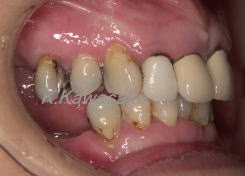

初診時

「全体的に虫歯が多く良く噛めない」と来院されました。

上下奥歯が無く前歯だけで噛んでいるため、前歯が前方に出てきてしまいました。 |

| ほとんどの歯に虫歯があり全体的に歯周病にもなっていました。また口元は前突感があります。全体的な治療が必要な状態です。 |